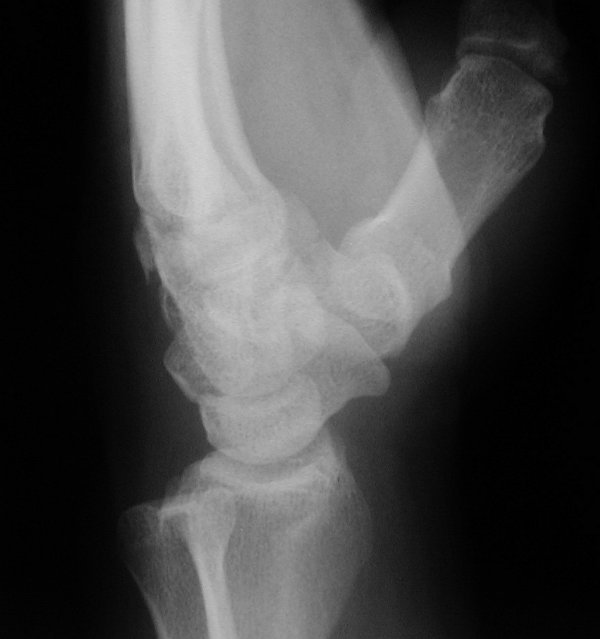

Return to Hamate Fracture